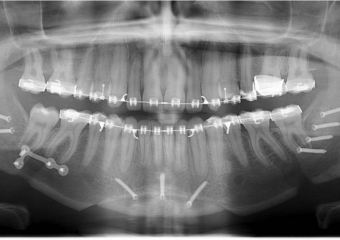

Raio x inicial